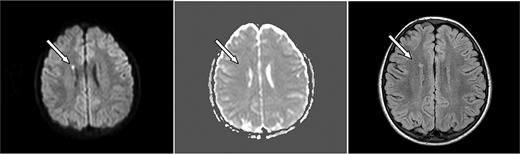

ASCIE were identified by DWI in 4 (18.2%) of 22 children with SCD and 2 (6.7%) of 30 without SCD (P = .382, Table 1). All had areas of restricted diffusion on DWI with corresponding areas of decreased signal on ADC map. There were corresponding abnormalities on the initial FLAIR images in 4 of 6. DWI lesions were subcortical or in the deep white matter (Figures 1–2). One patient had deep white matter DWI lesions and a lesion in the splenium of the corpus callosum without history of seizure. Two of the 6 patients had multiple DWI lesions, 4 had solitary lesions.

Axial MRI images of case 3. A 10-year-old girl with SCD and parvovirus infection with hgb = 2.9 g/dL showing (left, arrow) an area of restricted diffusion on DWI images with an ACD correlate (middle). Follow-up FLAIR MRI 7 months later (right) shows a lesion corresponding to the affected area on the DWI.

Follow-up MRI studies (Figures 1–2) were obtained 2.5 to 7 months later for other clinical indications for 4 of 6 of the patients with ASCIE; 3 had lesions on FLAIR images consistent with SCI in locations corresponding to the ASCIE on the initial study MRI (Table 1) and thus meet the definition of acute SCI. All 3 had SCD. Notably, the patient without a corresponding lesion on follow-up imaging also had no FLAIR correlate on the initial study MRI. This patient did not have SCD. We believe this to be a transient, reversible ASCIE.7 Magnetic resonance angiography (MRA) was not part of our study protocol but was obtained for the clinically indicated follow-up studies for 4 of 6 of the patients with ACSIE and was normal in 3, with 1 patient demonstrating subtle vascular irregularities in the internal carotid artery and middle cerebral artery ipsilateral to the ASCIE (Table 1).